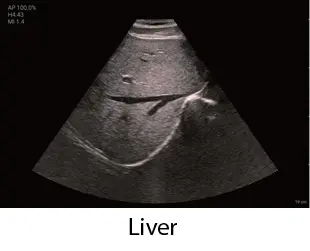

Чрез интегриране на множество приложения, TE Air e5M предлага сканиране на цялото тяло и се адаптира към различни клинични ситуации. Неговият безжичен дизайн осигурява възможност за извършване на ултразвукови изследвания с високо качество по всяко време и навсякъде. Освен своята универсалност, TE Air e5M предлага и редица интелигентни функции и обучителни инструменти, които повишават увереността и ефективността при работа.

Сканирайте цялото тяло с увереност

Абдомен, малки част, съдови, акушерство, гинекология, FAST и др

"как" и "какво" при извършване на ултразвукови изследвания. Включва анатомични илюстрации, стандартни ултразвукови изображения, референтни снимки за сканиране и съвети за умело извършване на диагностика. Обхваща приложения за корем, щитовидна жлеза, съдова система, малки части, урология, акушерство и гинекология, FAST протоколи, кардиология и нервна система.

Клинични снимки